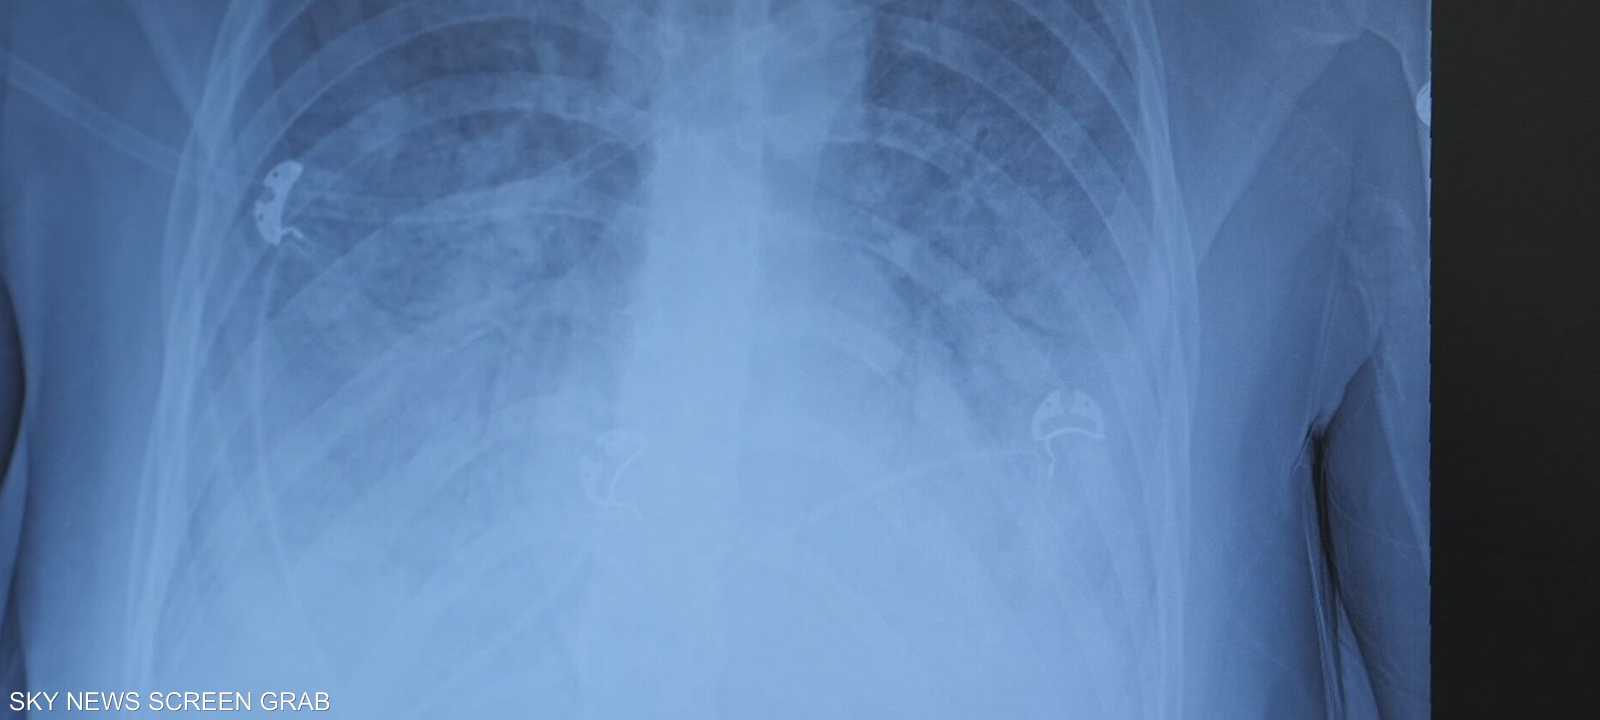

بعد عام من تدخين السيجارة الإلكترونية "الفيب" سرا دون علم أهله، أُصيب مراهق أردني يبلغ من العمر 16 عاما بحالة صحية خطيرة تعرف بـ"رئة الفشار" أو Popcorn Lung، وهي حالة نادرة تسببت له بتلف رئوي مزمن بات يستدعي استخدام الأوكسجين مدى الحياة.

ونقل المراهق إلى المستشفى في حالة طارئة بعد تعرضه لفشل رئوي حاد، لتشخص حالته بإصابة خطيرة في الرئتين منعته من التنفس دون دعم خارجي.

وأشار إلى أن تدخين "الفيب" والسجائر الإلكترونية يسبب نفس الضرر تقريبا الذي تسببه السجائر التقليدية، بما في ذلك التهابات القصبات الهوائية نتيجة التعرض لمواد سامة، وهو ما ظهر في حالة الفتى الأردني الذي أصيب بفشل رئوي كامل.